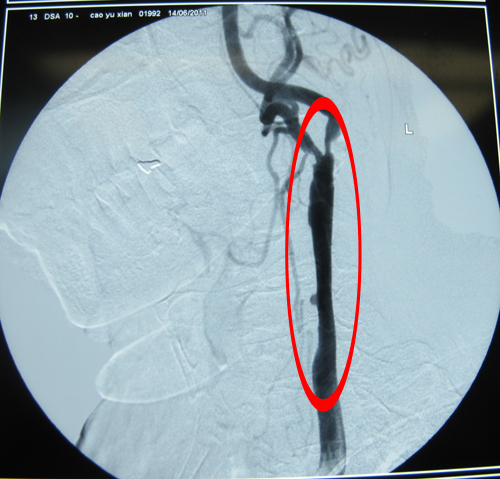

头颅CTA(同煤总医院,2011-5-30):颈动脉硬化性改变(左侧颈内动脉近段管腔中重度狭窄,右侧颈内动脉近段轻度狭窄)。

左侧颈内动脉起始段中重度狭窄,颈总动脉重度狭窄